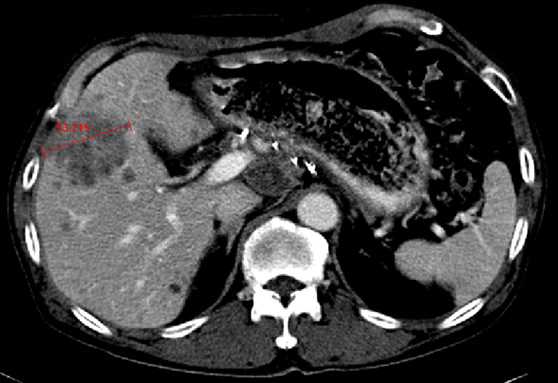

При оценке терапии гепатоцеллюлярной карциномы (ГЦК) следует пользоваться критериями mRECIST вместо RECIST. Оценка проводится при помощи КТ или МРТ, исключительно в артериальную фазу сканирования.

Применение mRECIST при оценке гепатоцеллюлярной карциномы. Оценка таргетного очага применительно только в артериальную фазу при компьютерной томографии (КТ). Согласно критериям RECIST идет подсчет суммы диаметров очагов. В дополнение согласно критериям mREСIST длинник очага оценивается в той части, что наиболее усилилась постконтрастно в артериальную фазу.

На верхних двух изображениях представлены после проведенного лечения (основная опухоль не представлена) первые повторные исследования в артериальной и венозной фазах, при которых выявлен очаг в размерах менее 1 см, что согласно критериям RECIST является не измеряемым. На вторых повторных исследованиях в артериальной и венозной фазах определяется очаг более 1 см с характерными признаками злокачественности (артериальной гиперваскуляризацией и венозным вымыванием), который является теперь измеряемым. В данном случае об прогрессировании заболевания после первого повторного исследования можно говорить только ретроспективно.